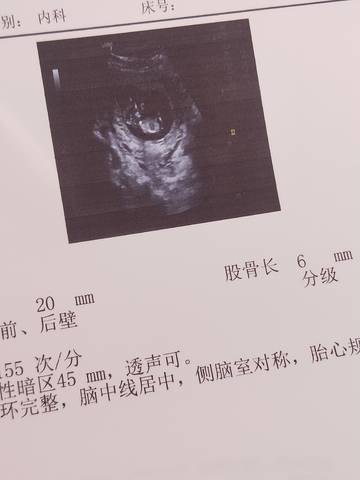

能看出来男孩女孩吗?我是看不出来头和屁股,很模糊

亲爱的,通过这些判断不出来是什么样性别的哈,反正宝宝发育好就是最好的哈,祝你好孕。

#妈妈问答大赛#看不出来男孩还是女孩的,这时候特别小,还是很模糊的